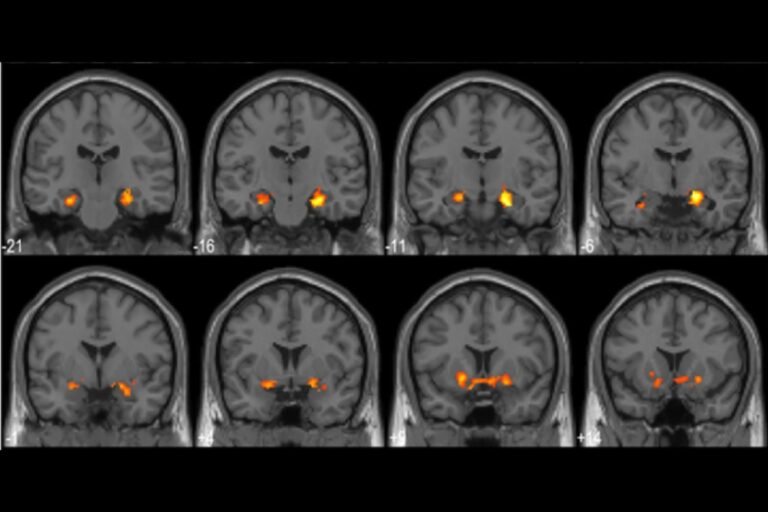

All of us had a moment, when the solution to a problem suddenly became obvious. In cartoons, that Eureca feeling is usually depicted as the lightblob floating above a character’s head – which is not too far from what actually…